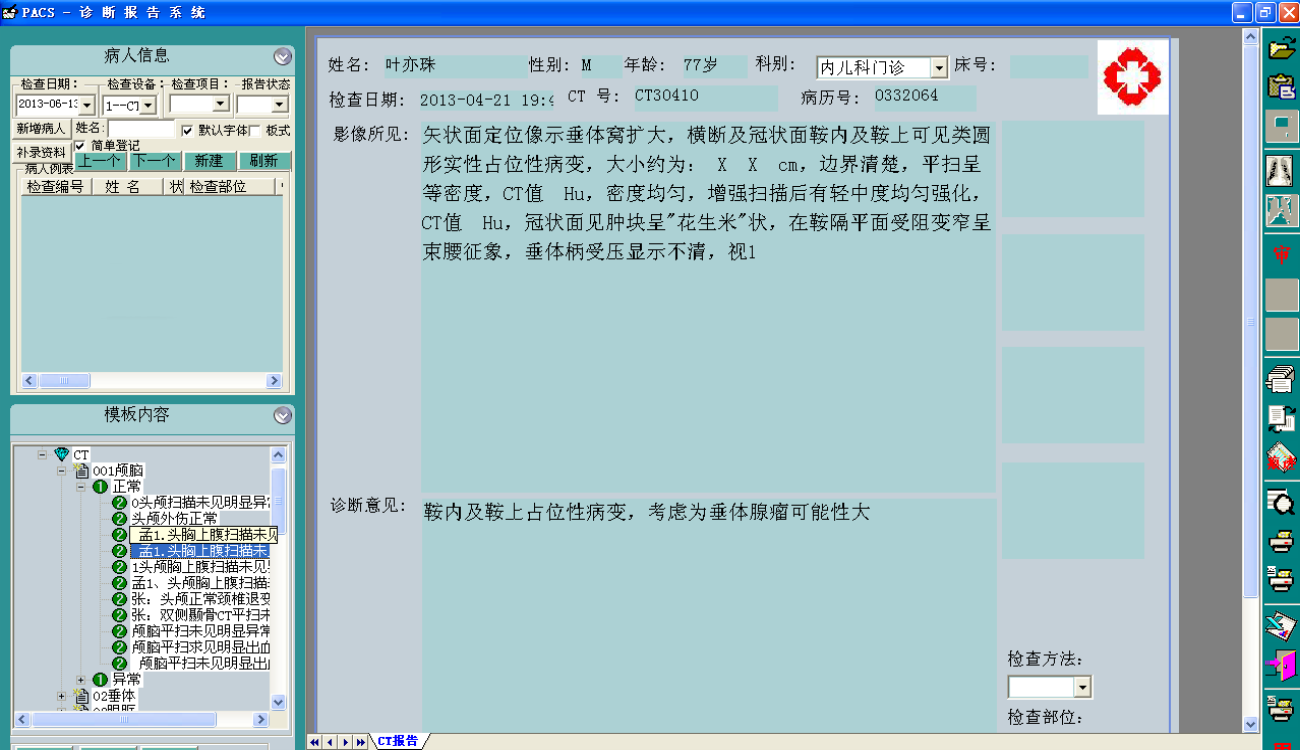

二、PACS影像系统源码,带三维重建和还原的PACS系统源码

三甲医院医学影像PACS系统源码,集成三维影像后处理功能,包括三维多平面重建、三维容积重建、三维表面重建、三维虚拟内窥镜、最大/小密度投影、心脏动脉钙化分析等功能。系统功能强大,代码完整。

1、C/S架构的PACS系统可实现检查预约、病人信息登记、计算机阅片、电子报告书写、胶片打印、数据备份等一系列满足影像科室日常工作的功能。

2、相关技术:C语言+数据库 : MSSQL+开发工具 : VC